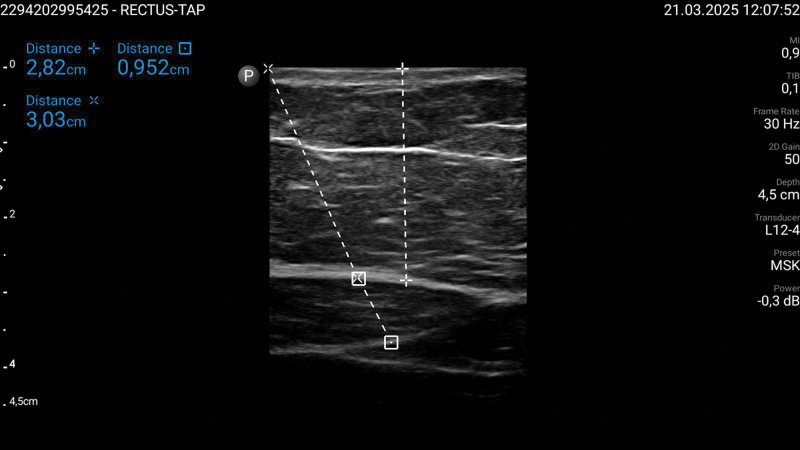

Recent findings: Current evidence supports the use of RA techniques such as transversus abdominis plane (TAP) block, quadratus lumborum (QL) block, erector spinae plane (ESP) block, and intraperitoneal instillation of local anesthetics in reducing postoperative pain and opioid consumption. While TAP and ESP blocks improve postoperative analgesia, the QL block offers longer-lasting pain relief. Intraperitoneal local anesthetic administration has shown potential in decreasing opioid use and improving respiratory recovery. Additionally, port-site infiltration remains a simple yet effective alternative. However, anatomical challenges in obese patients necessitate optimized ultrasound guidance for successful block placement.